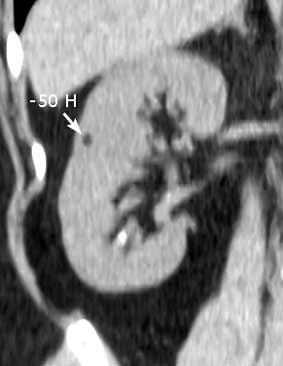

Случайная находка в нижней трети левой почки (не в полюсе, а по задне-медиальной поверхности).

ПО УЗ-семиотике образование соответствует ангиомиолипоме (AML). По правилам в таких случаях необходимо выполнить КТ, доказать преимущественно жировой состав опухоли, затем проводить УЗ-наблюдение.

Согласен. Именно с таким диагнозом (ангиомиолипома) отправил на КТ. Особенностью случая ИМХО является заметный "выход" образования за контур почки (на 2/3 объема).

При ультрасонографии ангиомиолипома выглядит как округлое образование без капсулы с однородной внутренней эхоструктурой и четкими контурами; эхогенность ее чаще всего равна или чуть выше эхогенности перинефральной клетчатки [7]. Значительно реже эхогенность ангиомиолипом может быть равна эхогенности почечной паренхимы; такие опухоли состоят почти полностью из гладкомышечной ткани [8]. Иногда позади ангиомиолипомы может определяться слабая акустическая тень.